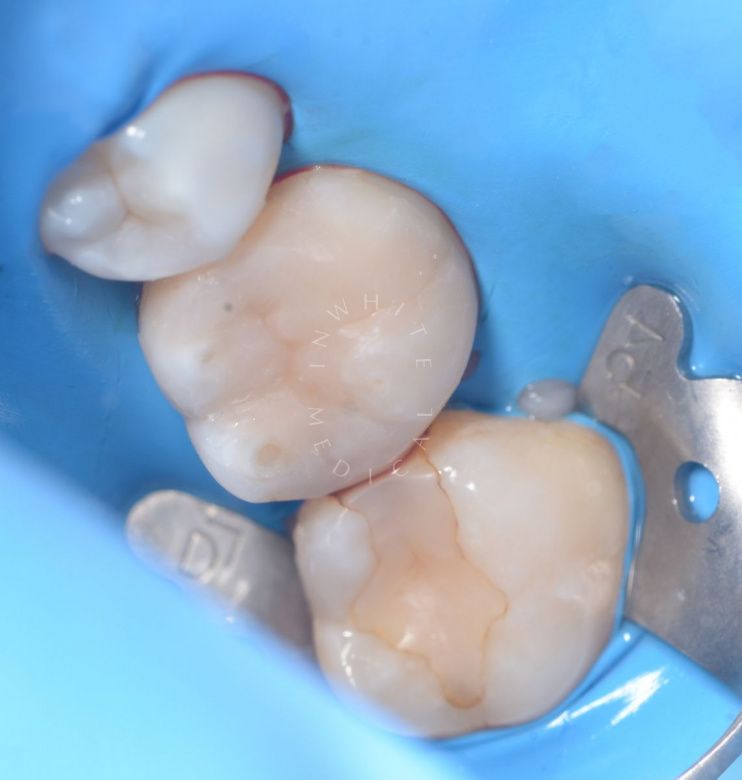

Лечение скрытого кариеса под старой пломбой

Результат

До После